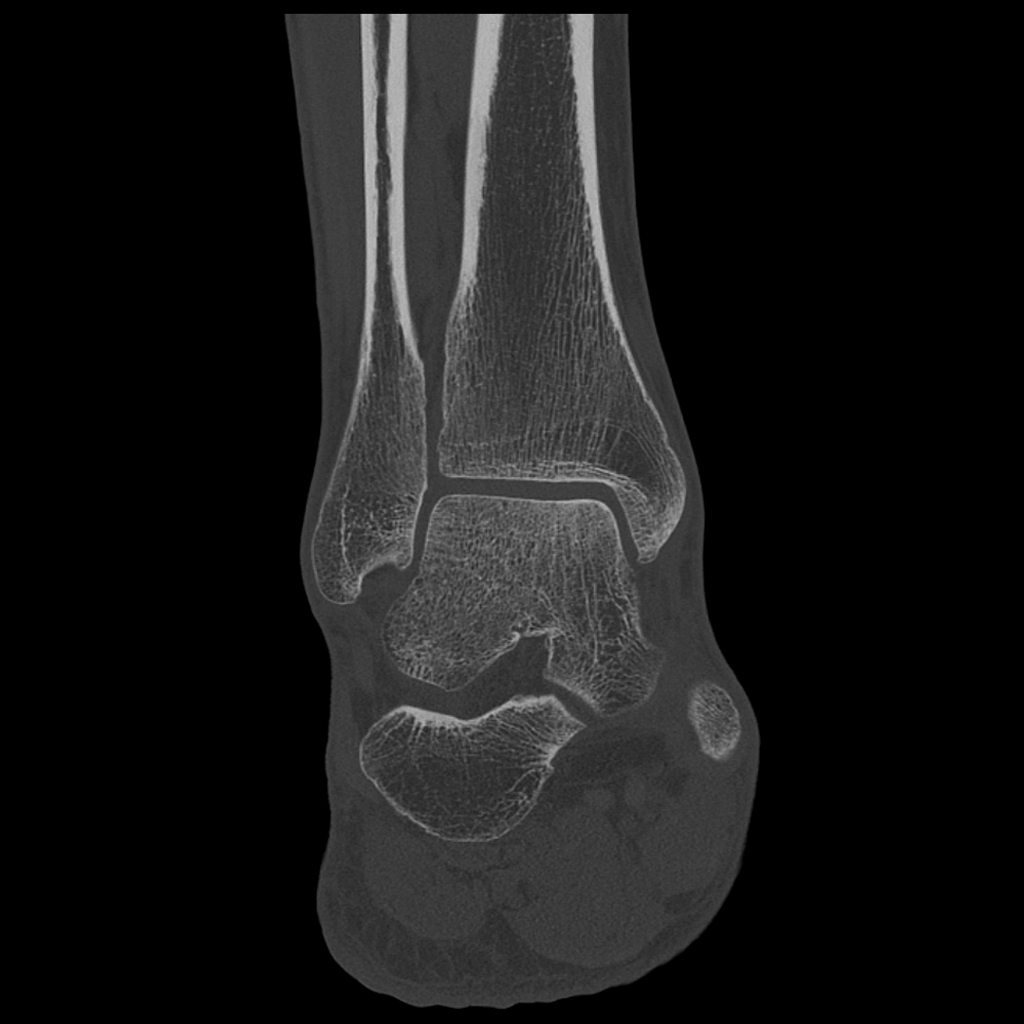

Порівняння звичайної роздільної здатності з ультрависокою роздільною здатністю (УРЗ)²

Звичайна КТ 0,5 мм

КТ з ультрависокою роздільною здатністю 0,25 мм ³